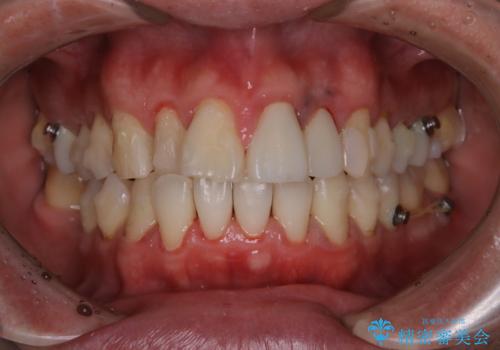

- インビザライン中に着色が気になるとのことでした。PMTC30分コースを行いました。

インビザライン治療中には、歯の表面にアタッチメント(効率的に歯の移動をするもの)を設定します。そのため歯ブラシでは届きにくい細かい部分などに、歯石や着色がついてしまうことがあります。着色などを放置していると、着色なのか、虫歯なのかの判別もしずらく正確にお口の中の状態を診断できません。

矯正治療中も定期的に歯科医院にてPMTCを受けて、お口のケアを行うことをおすすめします。